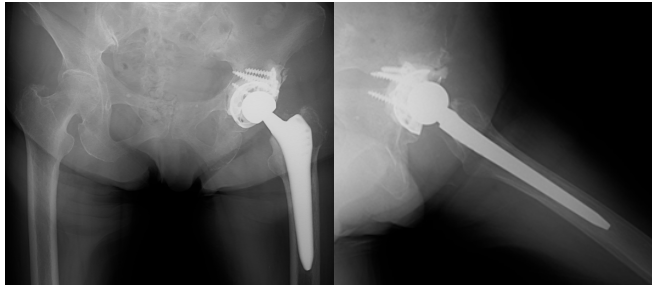

THA was performed using a posterior approach. Intraoperatively, soft-tissue consistent with metastatic tumor was identified in the acetabulum and removed as extensively as possible. The GAP II ring was applied to reinforce the acetabulum, and a cemented cup was implanted (Fig. 5).

Figure 5: Post-operative radiographs showing acetabular reconstruction using the restoration GAP II reinforcement ring and a cemented cup with stable fixation.